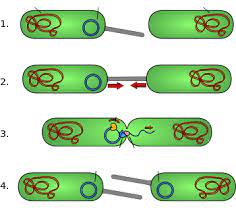

قیمت: 32٬000 تومان - دسته بندی فایل: علوم پزشکیپاورپوینت روش های انتقال ژن در بین باکتری ها

فروش ویژه پاورپوینت حرفه ای روش های انتقال ژن در بین باکتری ها با تخفیف استثنایی فقط 62453 هزار تومان تعداد اسلاید : 26 اسلاید